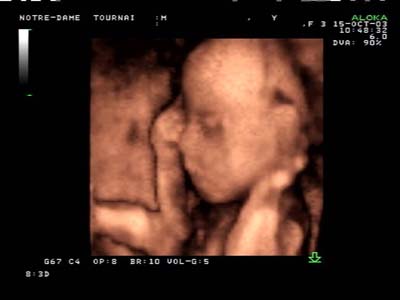

Analyse 3D : Echographie temps réel